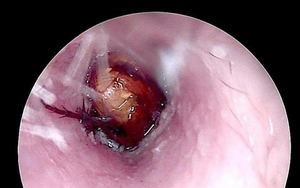

Cháu bé đau tai dữ dội, bác sĩ sốc ngang phát hiện bí mật

Nam thanh niên 15 tuổi đau bụng dữ dội, bác sĩ sốc khi phát hiện thứ "đáng sợ" bên trong - Ảnh 4.